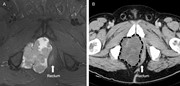

Cylindroma-like basaloid anal cancer presenting as a large pelvic mass in a patient with ulcerative colitis

Sugong Chen and others

Journal of Surgical Case Reports, Volume 2015, Issue 7, July 2015, rjv093, https://doi.org/10.1093/jscr/rjv093